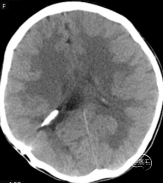

就诊时,①按压右耳后分流储液囊,回弹较缓慢,我们初步判断分流装置的脑室端还是通畅。②为判断腹腔端是否通畅或被包裹部分通畅?我们2次间隔8小时复查腹部平片(如下图),间接提示腹腔端较通畅。③入院时通过颅脑X光平片提示:分流管装置为贝朗(蛇牌),于是复核脑室腹腔分流阀(蛇牌),压力为10档,予以上调分流阀压力至11档,同时继续予以“甘露醇”降颅压,患儿症状明显较前缓解,偶有头痛,疼痛尚可忍受。

2022.04.15 2022.04.16